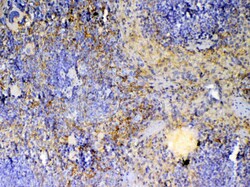

Reconstitute with 0.2 mL of distilled water to yield a concentration of 500 μg/mL. Positive Control - WB: mouse stomach tissue, mouse spleen tissue, mouse thymus tissue, mouse small intestine tissue, rat thymus tissue, human placenta tissue. IHC: mouse spleen tissue, mouse thymus tissue, rat spleen tissue.

| ELISA, Immunohistochemistry (Paraffin), Western Blot | |